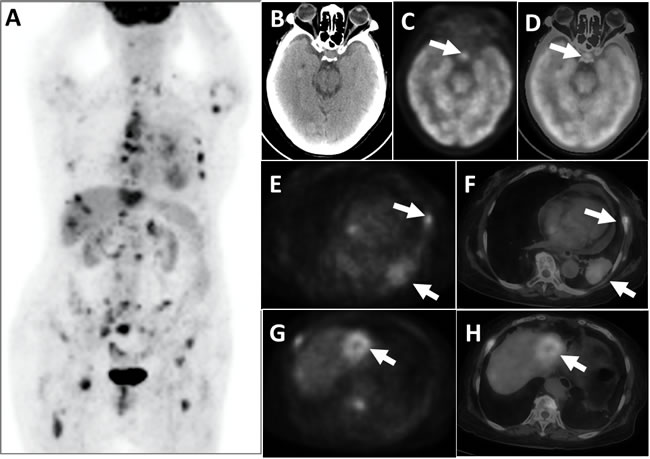

Finally, three cases of malignant tumor combined with systemic metastases and pituitary hypermetabolism were detected. The primary tumors were one endometrial cancer, one lung cancer, and one scalp melanoma, respectively, with associated pituitary SUVmax ranged from 7.3 to 32.3 (mean = 16.0 ± 10.6). There was corresponding abnormal uptake in these primary malignant sites.

Figure 3: This patient suffered from lung cancer, combined with multiple systemic metastases, had pituitary hypermetabolism. PET whole-body images (MIP) appeared multiple hypermetabolic A. PET cross-sectional imaging and CT fusion images revealed space-occupying lesions on the left lower lobe of the lung combined with adjacent rib bone destruction and hypermetabolism E. and F., white arrows); a space-occupying hypermetabolism was visible on the left liver lobe G. and H., and liver metastasis was suspected (white arrows). Brain PET C., CT B., and the fusion of cross-sectional tomographic images D. revealed that the pituitary exhibited FDG hypermetabolism (white arrows), with an SUVmax of 7.3.

One out of the 3 patients in this study who showed systemic metastases of malignant tumors (Figure 3) developed diabetes insipidus. It is difficult to differentiate pituitary metastases from pituitary tumors based on an 18F-FDG PET/CT-derived SUVmax. Reliable diagnosis might be generated by taking the local infiltration in the sella area, the patient’s clinical history, and other imaging data into account. All of the 3 patients had corresponding abnormalities of their malignancies on the whole body PET/CT scan, which facilitated the pituitary metastasis diagnosis.